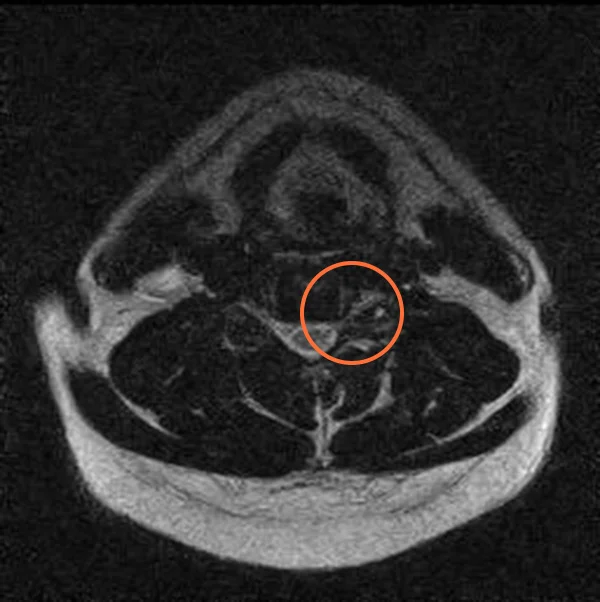

Foraminal Stenosis Mri Axial

The borders of the foramin are the disc in the front and the facet joint in the.

Foraminal Stenosis Mri Axial - Occurs between the medial and lateral border of the pedicle.